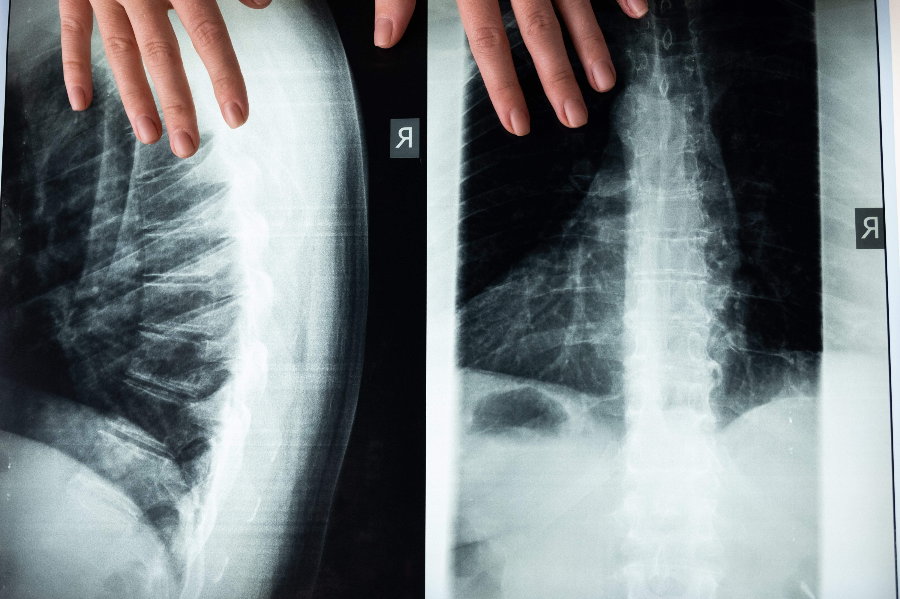

근골격계 질환도 척추에 영향을 미쳐 척추 측만증, 추간판 탈출증, 척추 협착증과 같은 질환을 유발합니다. 이러한 장애는 자세, 척추 정렬, 신경 기능에 영향을 미쳐 통증과 신경학적 증상을 유발할 수 있습니다.